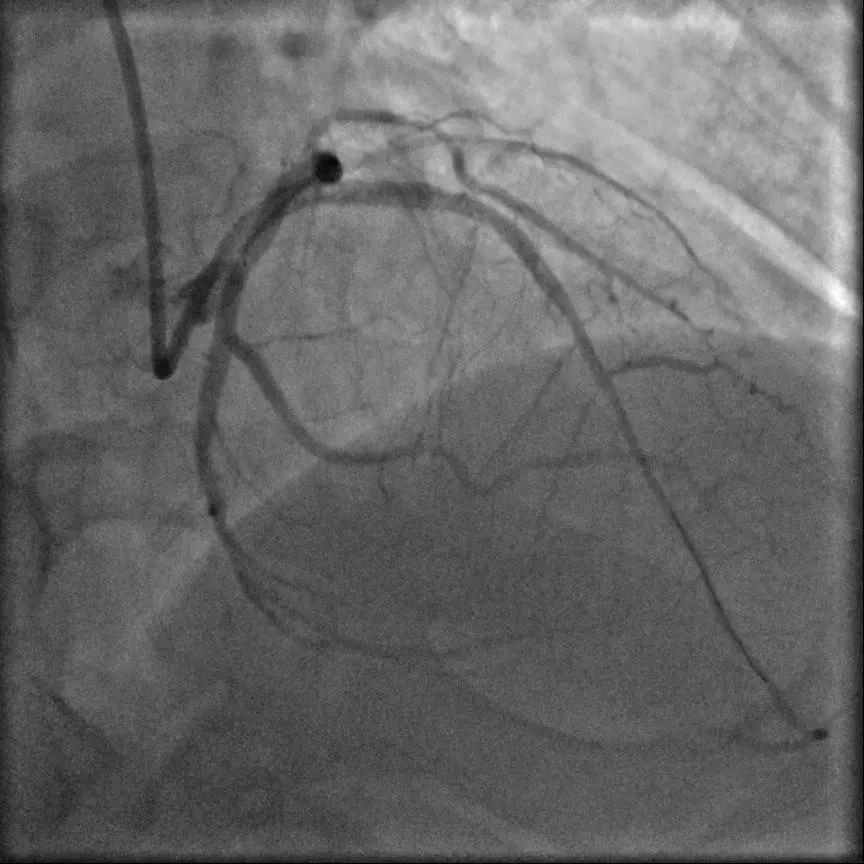

据了解,该患者今年四月因急性心梗在我院进行急诊PCI治疗,于RCA顺利放置支架3枚,术中冠脉造影检查提示前降支(LAD)开口起100%慢性闭塞。这种情况不处理,患者心功能势必受到影响,并有猝死风险。

6月6日,北京首都医科大学附属北京安贞医院及我院复杂冠脉病变治疗中心主任赵林教授与我院手术团队认真仔细研究了该患者的病史及影像资料,发现他的前降支开口齐头闭塞、闭塞段长度大于20mm、严重钙化、病变开口成角大,J-CTO评分为4分,这种病变开通难度大、开通成功率极低。

面对困难,赵林教授知难而上、勇于挑战。他首先尝试在IVUS指导下寻找正向开口,在IVUS无法提供支持的情况下,果断改用在微导管支持下逐渐升级导丝寻求正向突破。由于前降支开口成角大,近段纤维帽致密,反复调试导丝都未能突破。赵林教授凭借丰富的经验,逐渐升级导丝硬度再次反复尝试突破病变。锲而不舍、金石可镂,ConquestPro导丝最终在一瞬间突破病变,送至远端血管真腔,在助手及导管室工作人员的全力配合下,顺利开通病变。手术成功完成,术后患者无不适及并发症发生。

术中